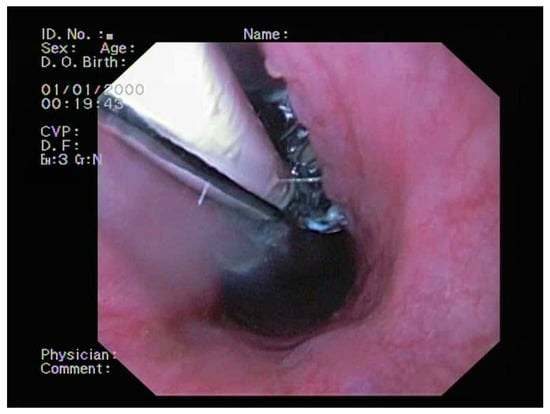

2.2. Bronchoscopy

2.4. Treatment